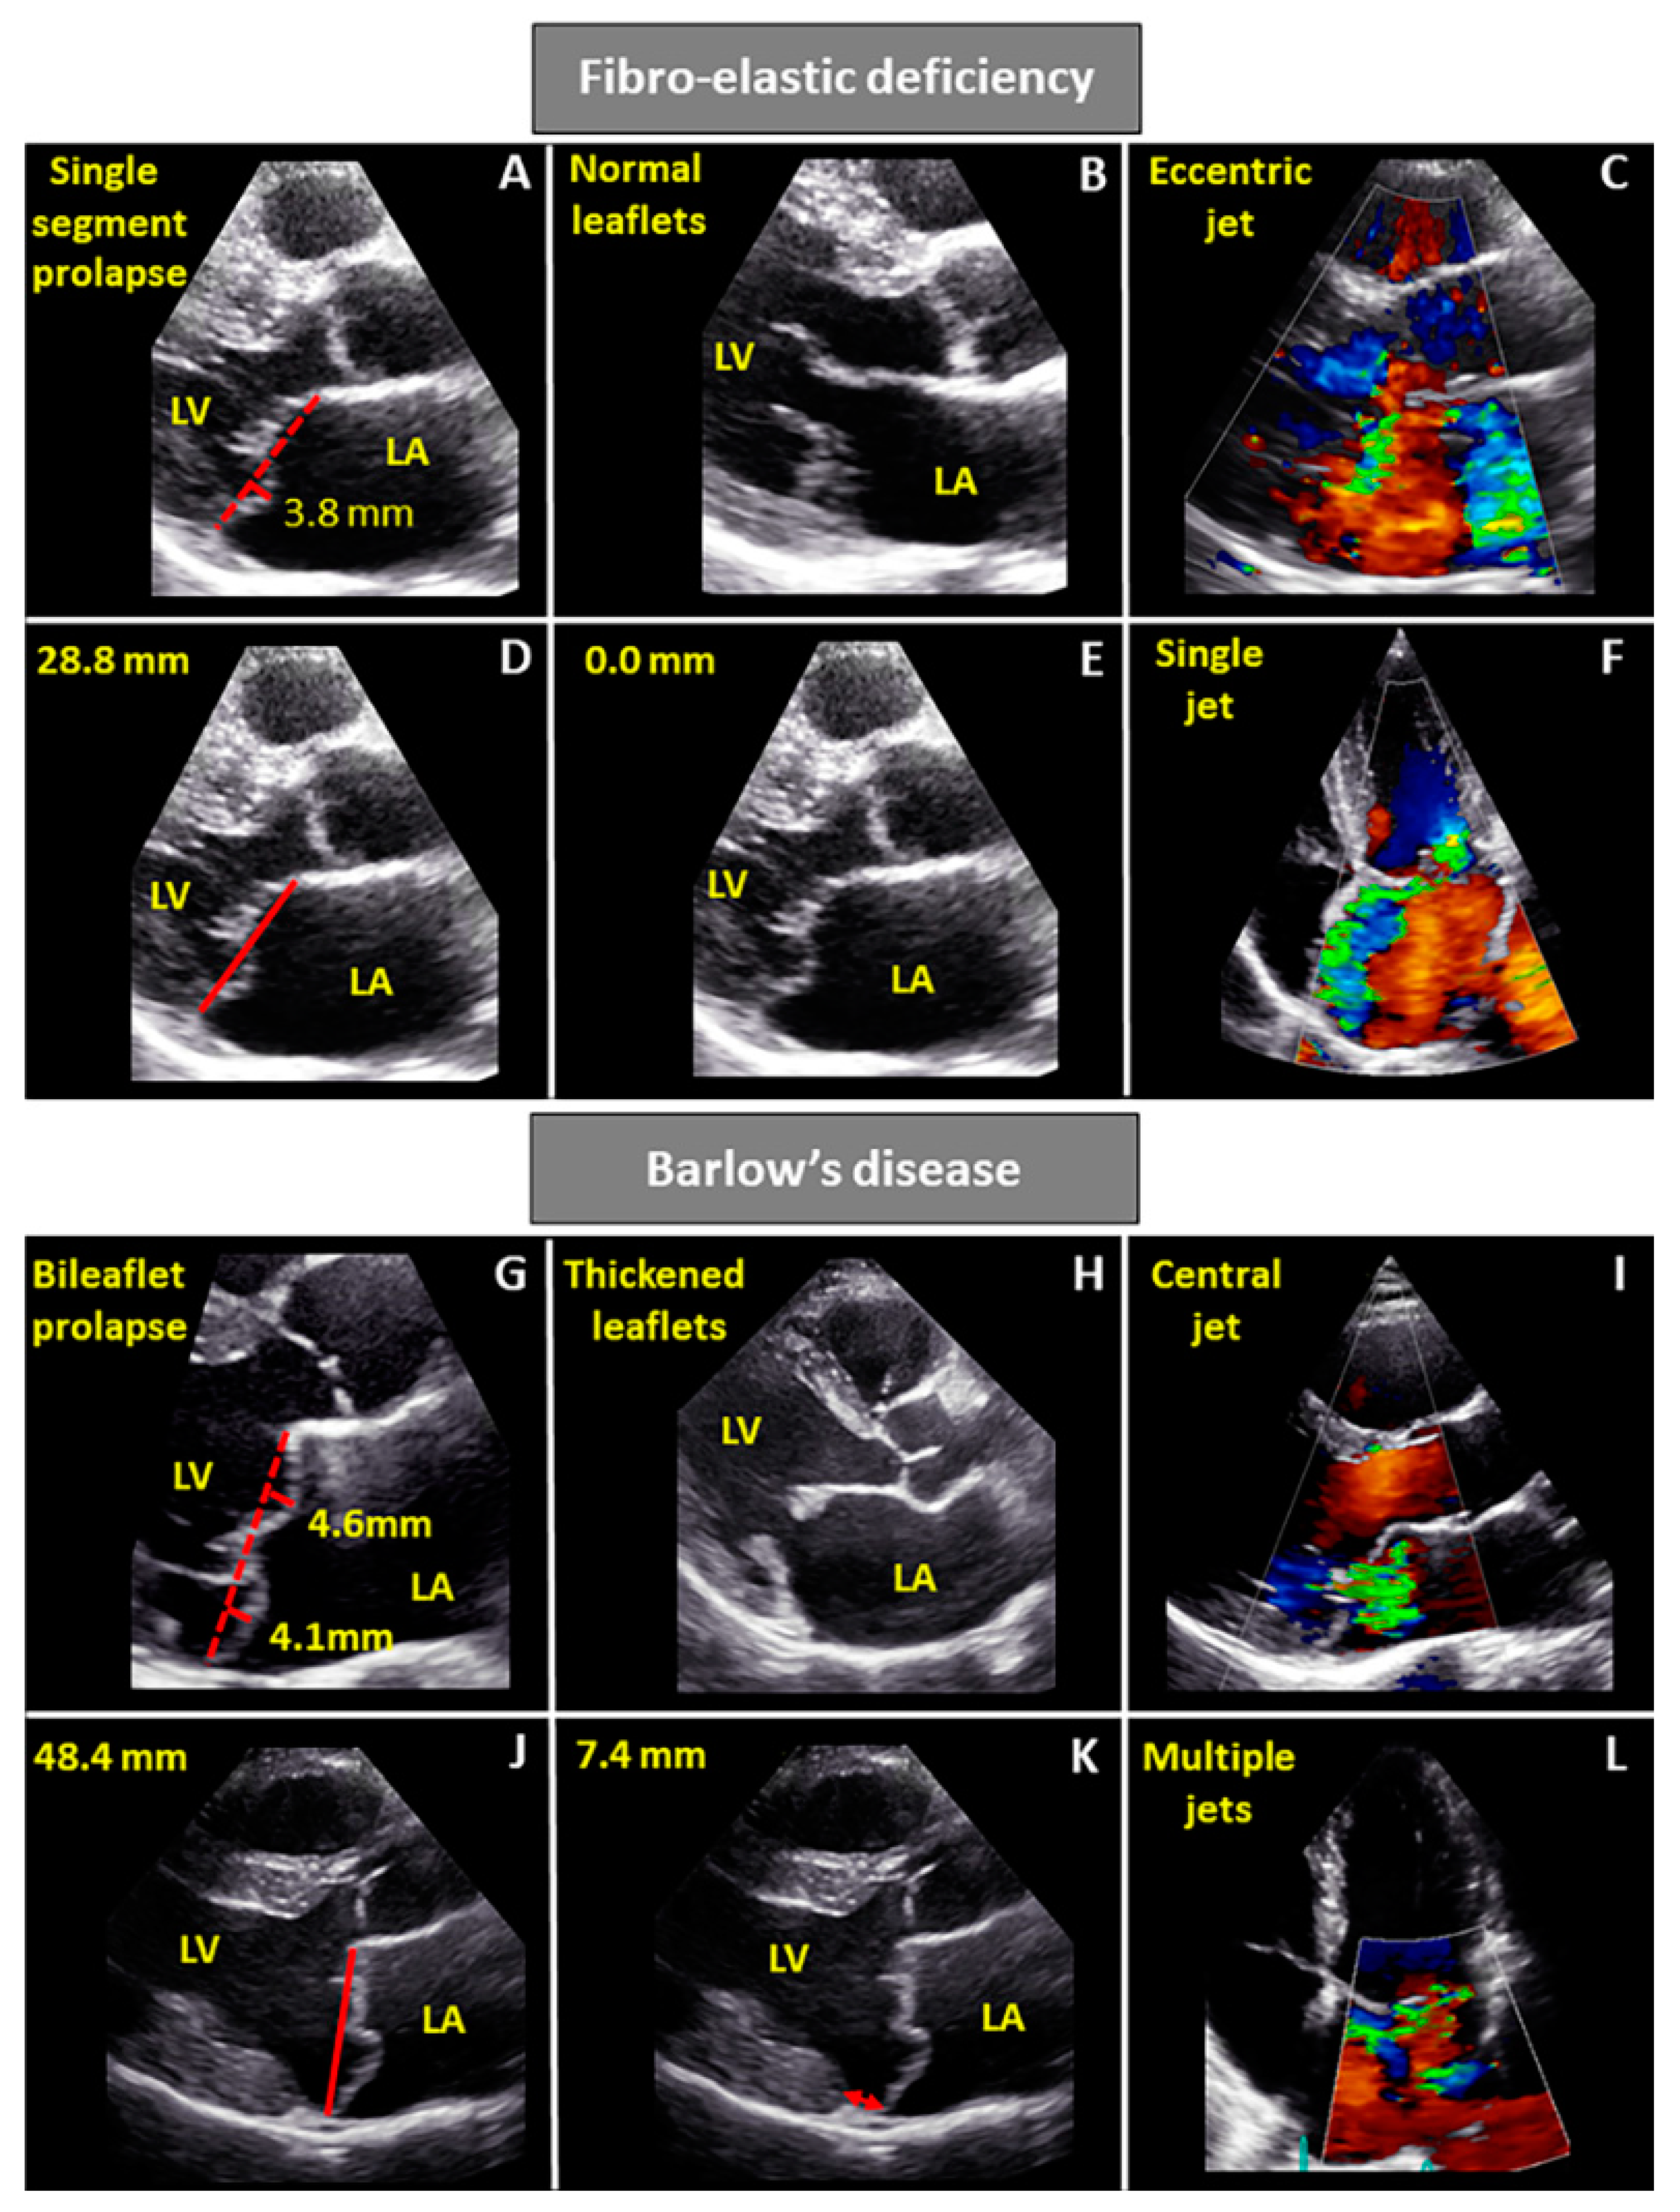

6. Echocardiographic Characteristics

| Leaflets | Single segment (usually posterior) prolapse (flail) due to chordal rupture Thickened leaflet tissue (when present) is limited to the level of the prolapsing segment Thin/normal leaflet tissue in non-prolapsing segments | Diffuse excessive valve tissue with multiple segments, bi-leaflet prolapse Thickened leaflets |

| Annulus | Normal of moderate annular dilatation No calcifications | Severe annular dilatation Calcifications could be present Mitral annular disjunction Systolic outward motion during systole (curling) |

| Chordae | Chordal rupture of the involved segment | Elongated or ruptured Thickened and/or calcified |